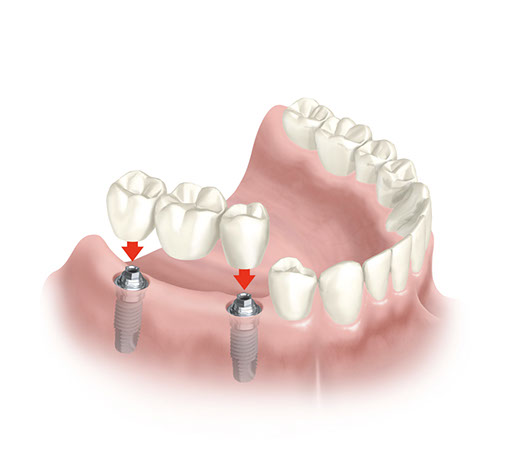

Tolta definitivamente la Vite di Guarigione si avvitano i Pilastri, ciascuno per ogni Impianto.

Ogni Pilastro farà da sostegno alla Protesi.

sostituire singoli denti, senza coinvolgere i denti vicini, così come avveniva in passato quando non esisteva alternativa alla realizzazione di un Ponte.

sostituire una Protesi Amovibile costruendone una Fissa grazie al posizionamento di nuovi elementi di fissaggio.